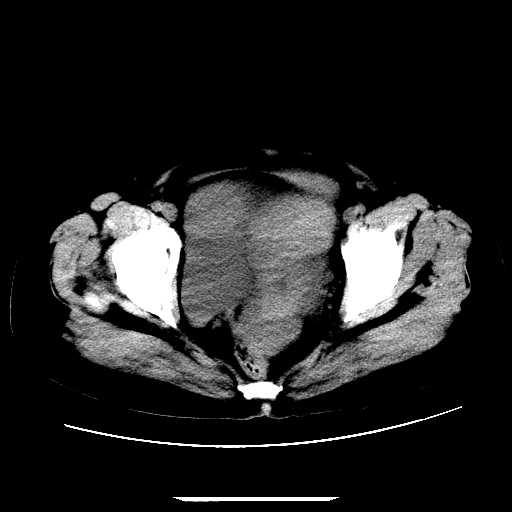

f,45y.怀孕4月晕倒,b超提示死胎,有手术结果,请展开讨论后明天告诉。

膈下-肠间隙内见气体密度影,子宫轮廓显示不清,宫腔-腹腔积液,首选考虑---子宫破裂出血。

1)宫腔妊娠。2)子宫破裂出血,腹腔及盆腔积血。

感谢同行们的高见。手术结果:子宫破裂出血。

我们的诊断是:腹、盆腔积液(考虑腹盆腔脏器破裂出血);宫腔妊娠。让人纳闷的是当时我们没有经验,现在回头看看分析:4月宫腔妊娠:1、洋膜囊不可能紧贴胎体这么小;2仔细看看子宫后壁肌层模糊不清;3腹、盆腔液体来源原因?4、45岁高龄妊娠有晕倒。由此可大胆诊断:宫腔妊娠子宫破裂出血。